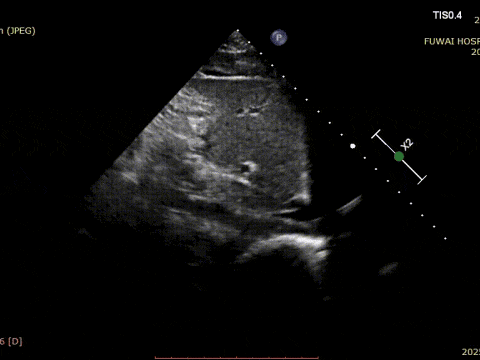

1. The ASD was central in location, with a measured diameter of approximately 8.1 mm (bicaval view) and 8.2 mm (aortic short-axis view).

4. There was no aortic rim, and the inferior and posterior rims were relatively soft.